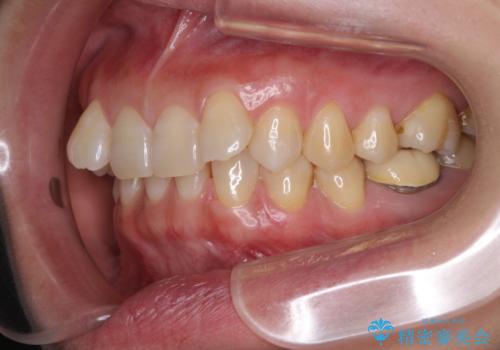

下顎2前歯の欠損 インビザラインによる抜歯矯正

③上顎左右第一小臼歯2本を抜歯し、下顎はスペースを閉じる

いずれもワイヤー矯正が望ましい治療方法ですが、家が遠方であり、近い将来出産される予定もあるとのことで、何とかマウスピース矯正でも対応可能な③にて治療を行うこととしました。

マウスピースでの抜歯矯正特有の抜歯スペースに向かって奥歯が傾斜する動きが顕著に表れ、ディープバイトは改善されませんでした。

前歯のみが強く接触し、奥歯で咬めない期間も続いたため、ワイヤー装置などを補助的に使用し、何とか終了させることができました。